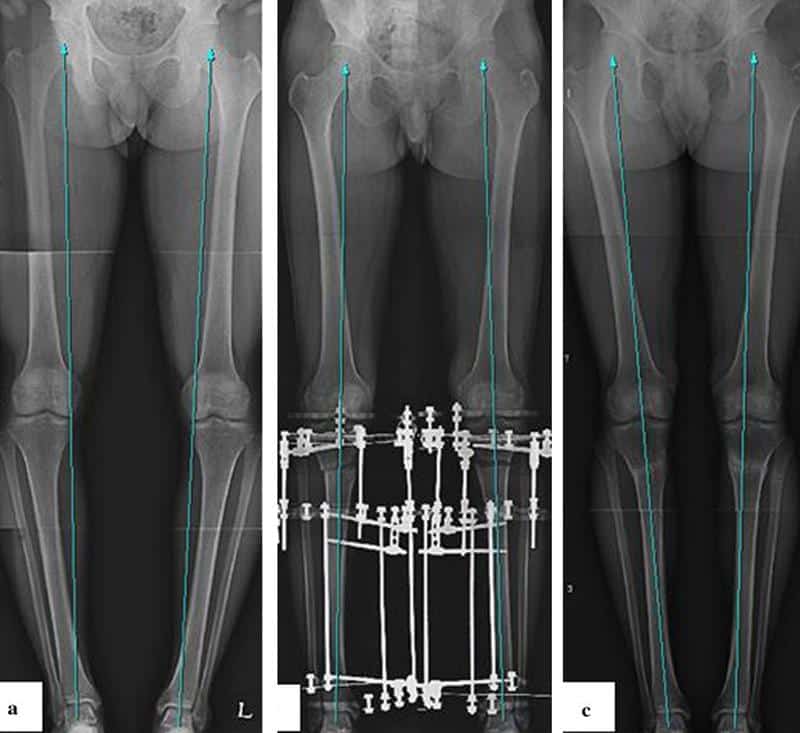

Врачи подчеркивают, что лечение варусной и вальгусной деформации голеней требует комплексного подхода. На начальных стадиях важно проводить консервативную терапию, включая физиотерапию, лечебную физкультуру и использование ортопедических стелек. Эти методы помогают улучшить положение суставов и укрепить мышцы. В случае более выраженных деформаций, специалисты рекомендуют хирургическое вмешательство, которое может включать остеотомию или артродез. Важно, чтобы лечение проводилось под контролем опытного ортопеда, который сможет оценить степень деформации и подобрать оптимальную методику. Регулярные осмотры и мониторинг состояния пациента также играют ключевую роль в успешном восстановлении.

| Варусная деформация (О-образные ноги) | Консервативное лечение (лечебная физкультура, ортопедическая обувь, ортезы), оперативное лечение (остеотомия) | Деформирующий артроз коленного и голеностопного суставов, боли в суставах, ограничение подвижности, нарушение походки, повышенная нагрузка на внутренние отделы коленных суставов |

| Вальгусная деформация (Х-образные ноги) | Консервативное лечение (лечебная физкультура, ортопедическая обувь, ортезы), оперативное лечение (остеотомия) | Деформирующий артроз коленного и голеностопного суставов, боли в суставах, ограничение подвижности, нарушение походки, повышенная нагрузка на наружные отделы коленных суставов |

Лечение варусной деформации голени у детей и взрослых осуществляется различными способами, которые зависят от степени тяжести заболевания и его запущенности. Например, для детей младше трех лет рекомендуется курс физиотерапии, массаж, лечебная гимнастика и использование специальной ортопедической обуви. Мягкую обувь лучше исключить, а предпочтение отдать хождению босиком.